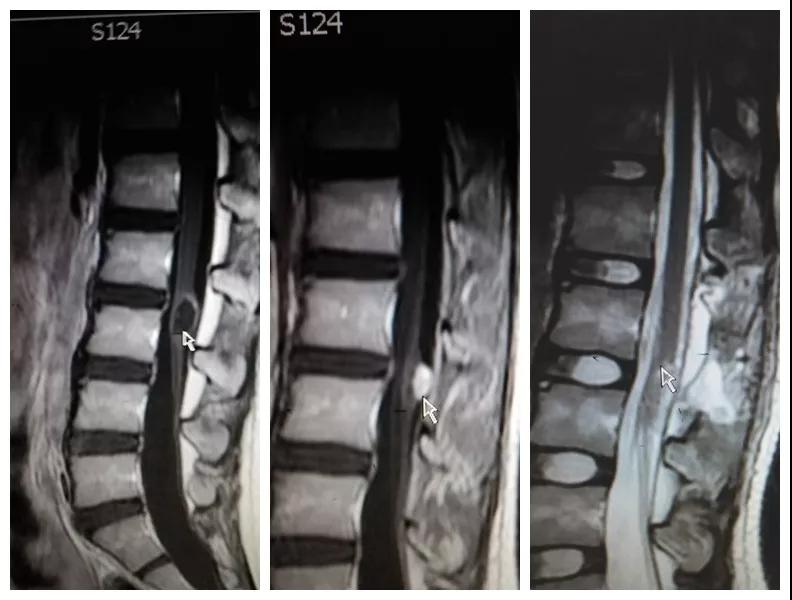

2018年8月,孩子母亲带着一线希望慕名找到色花堂 神经外科王占尧主任医师。王医生通过详细询问病史、查体、完善相关检查后,明确诊断患者为腰3椎管脊髓内畸胎瘤、硬脊膜外脂肪瘤、脊髓栓系综合症、骶尾部皮毛窦。王占尧耐心与家属沟通病情及手术方式,因手术难度大费用较高患者家属有些犹豫,随后又到西安多家医院咨询,最终选择在中心医院神经外科手术。因患者椎管处有不同部位的四个病变,还伴脊髓内畸胎瘤,分几次手术安全性高但是存在再手术医疗费用高、住院时间长耽误孩子上学等问题,如果选择一次手术切除则存在手术时间长、肿瘤是否能最大限度的全切、污染手术与清洁手术同时进行等系列问题。王占尧主任医师组织医疗团队反复讨论患者病情、斟酌手术方式、评估手术风险、制定详细的手术方案,最终决定在全麻下一次手术为患者同时切除四个病变部位。孩子的父母是一辈子面朝黄土背朝天的农民,面对术前谈话时主管医生提到的种种风险,他们不能完全理解,只是落泪重复:“孩子是我两的希望,我们就把孩子交给你了王大夫!”王占尧正是承受着一旦手术失败,孩子可能原有症状加重、甚至终身大小便失禁、双下肢瘫痪的压力,带着孩子父母沉甸甸的希望走进手术室。

手术很成功。术后孩子恢复非常好,未出现并发症,复查磁共振肿瘤切除干净,大小便失禁症状较术前明显好转,腰部疼痛也得到了缓解,目前已痊愈出院。